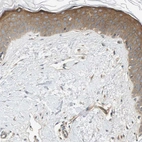

Immunohistochemical staining of human skeletal muscle shows strong cytoplasmic positivity in myocytes.